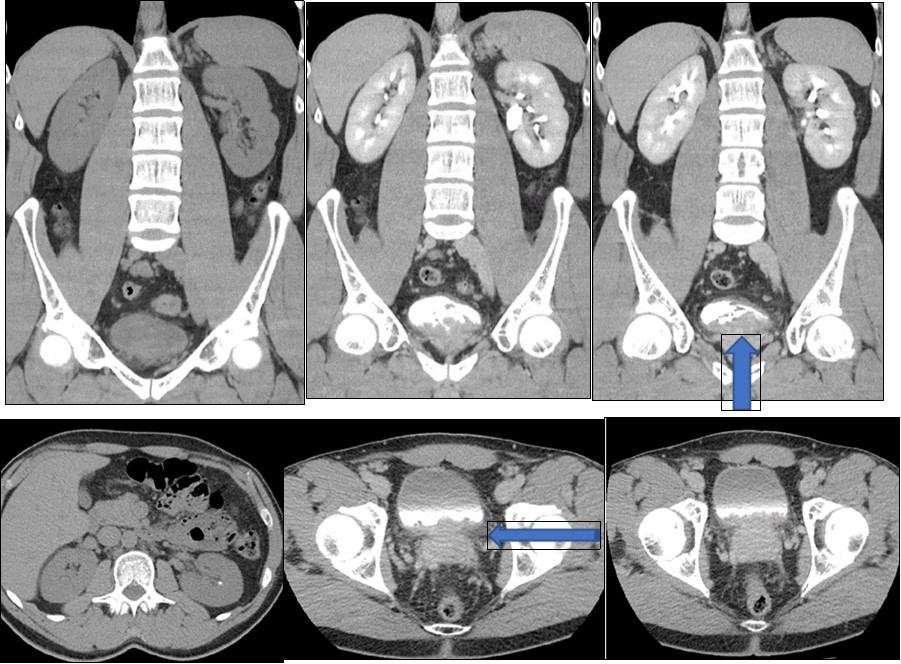

A young 38-year-old man, with no pathological history, consults for cystitis evolving for 4 months. The patient's clinical examination is normal. Laboratory test results and urine studies were unremarkable. The abdomin-pelvic ultrasound revealed an echogenic intra vesical tissue structure of its lower part, 2 cm thick. Thickening of the bladder wall without bilateral ureteropelocalitial dilation. The prostate is normal. The tomodensitometric examination (CT) finds a vegetative mass of the homogeneous bladder floor increasing after injection of contrast product which extends towards the left ureteral meatus without uretero-hydronephrosis. The posterior wall of the bladder is thickened with invasion of the inter vesical-prostatic fat. The rectal perineal fat was respected. No retro peritoneal or pelvic lymphadenopathy (Figure 1). Calculation of the left kidney of 2 mm non obstructive. Kidney function and morphology are normal. Cystoscopy shows a solid, polyp-like lesion covered with normal looking mucosa that has been completely resected.

(Figure 1), vegetative mass of the homogeneous bladder floor increasing after injection of contrast product extends to the left ureteric meatus without uretero-hydronephrosis. The posterior wall of the bladder is thickened without invasion of the inter vesico-prostatic fat (large arrow). The rectal perineal fat was respected. Calculation of the left kidney of 2 mm non obstructive (fine arrow).